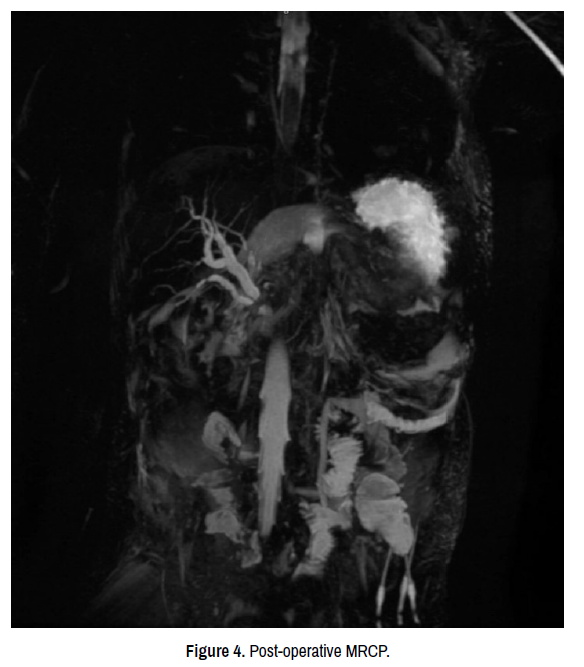

Due to the patient’s persistent vomiting, an upper gastrointestinal study was performed showing a large, distended stomach, with accentuated peristaltic movements, but no passage of the contrast substance at 20 minutes after administration. Following abdominal radiographs showed no progression of the contrast substance at 1 and 3 hours after administration and minimal passage at 6 hours after administration (Figure 1). Following the upper GI study, the patient’s general condition worsened with persistent, cramp abdominal pain, loss of appetite, abdominal distension and inability to have bowel movements or flatulence. The decision was made to perform emergency laparotomy for intestinal occlusion, most likely due to intestinal adhesions following omphalocele surgery.

clinical-case-reports-post-operative

Figure 1. Upper GI contrast study 1 hour, 3 hours, 6 hours, post-operative.